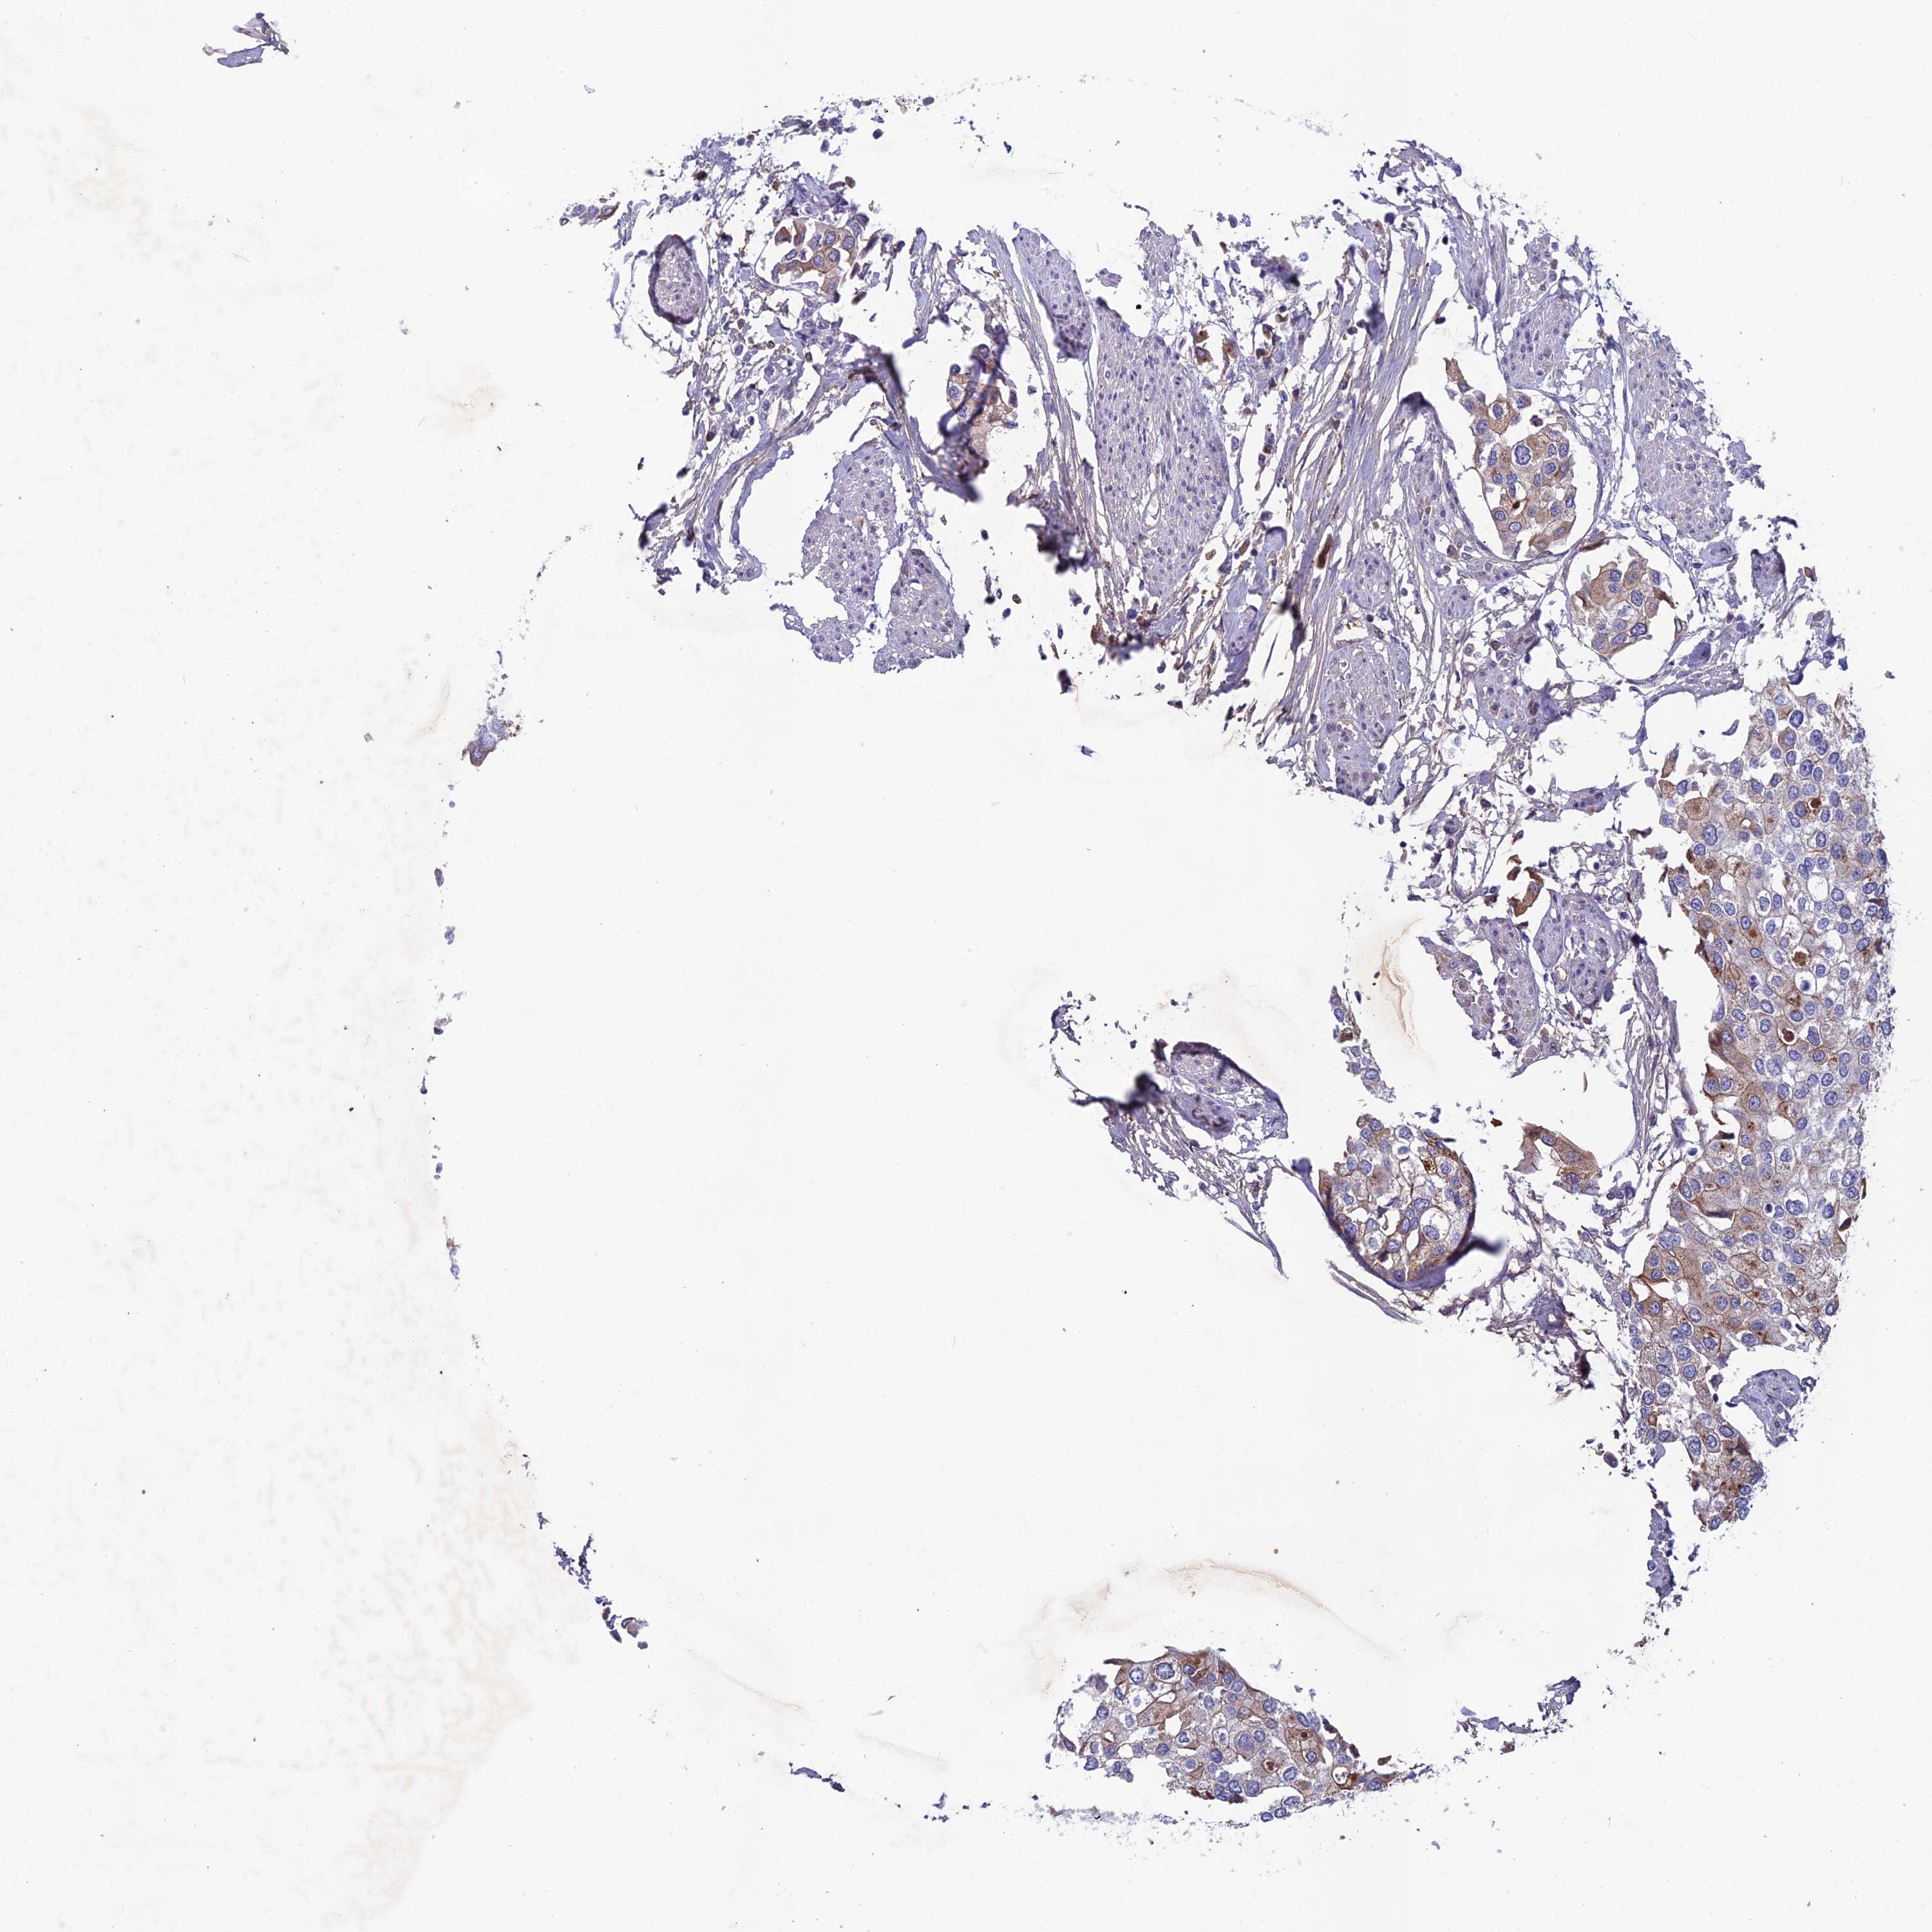

UROTHELIAL CANCER - Protein expressioni

A mouse-over function shows sample information and annotation data. Click on an image to view it in a full screen mode. Samples can be filtered based on level of antibody staining by selecting one or several of the following categories: high, medium, low and not detected. The assay and annotation is described here.

Note that samples used for immunohistochemistry by the Human Protein Atlas do not correspond to samples in the TCGA dataset.

Antibody stainingi

Antibody staining in the annotated cell types in the current human tissue is reported as not detected, low, medium, or high, based on conventional immunohistochemistry profiling in selected tissues. This score is based on the combination of the staining intensity and fraction of stained cells.

Each image is clickable and will lead to virtual microscopy that enables deeper exploration of all samples and also displays staining intensity scores, fraction scores and subcellular localization as well as patient and tissue information for each sample.

Antibody HPA043478

Staining

High

Medium

Low

Not detected

Intensity

Strong

Moderate

Weak

Negative

Quantity

>75%

75%-25%

<25%

None

Location

Nuclear

Cytoplasmic/membranous

Cytoplasmic/membranous,nuclear

Urothelial carcinoma, High grade

Urothelial carcinoma, Low grade